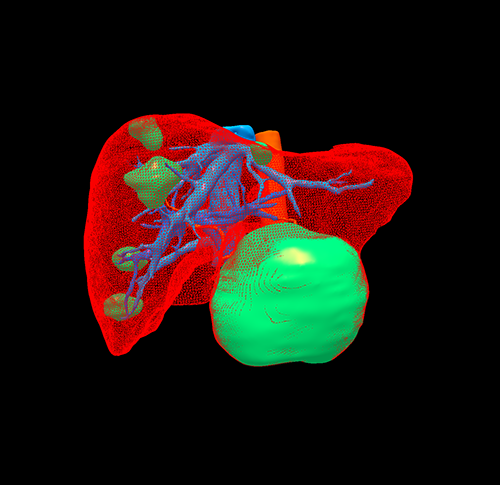

肝血管瘤--左肝外侧叶切除